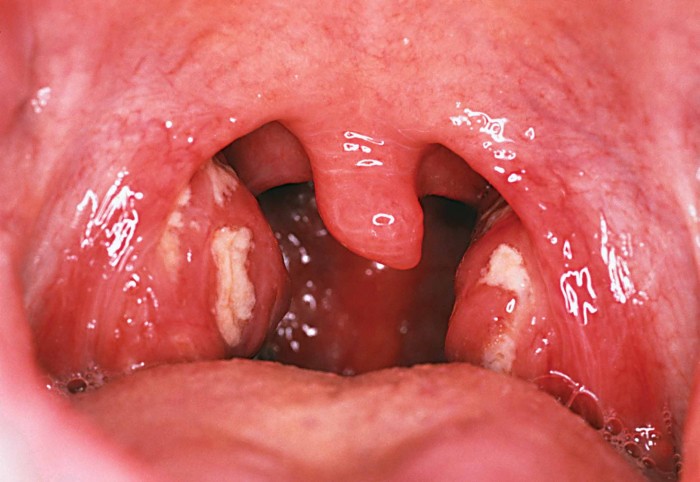

Как выглядит горло с хроническим тонзиллитом?

При ангине небные миндалины обычно ярко-красные, увеличенные, с видимыми белыми или желтыми пробками или налетом, сопровождающимися неприятным запахом. При хроническом тонзиллите миндалины также могут быть увеличены, но часто покрыты рубцами, спайками, что характерно для длительного воспалительного процесса.

Диагностика тонзиллита. Если миндалины увеличены, их ткань разрыхлена, покраснела, есть утолщения, отеки, рубцовые ткани, бороздки, гной (особенно с неприятным запахом), творожнообразные выделения и др., это может говорить о наличии хронического тонзиллита.

Во время осмотра ЛОР выявляет такие признаки хронического тонзиллита:

- Миндалины срастаются с нёбными дужками.

- В лакунах образованы гнойные пробки, содержащие лейкоциты, слизь и продукты жизнедеятельности бактерий.

- Структурное изменение анатомии миндалин.

- Покраснение и отёчность миндалин.

- Регионарные лимфоузлы увеличены.

Когда наступает обострение, у ребёнка повышается температура тела, общее самочувствие ухудшается. При осмотре горла малыша обнаруживается большое количество гноя в лакунах миндалин.